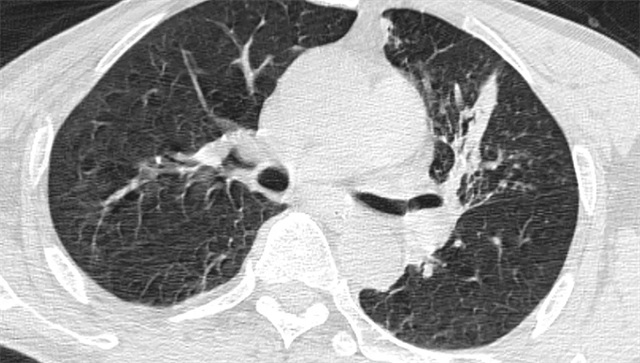

术后,医护团队为郑大爷制定了个性化的治疗方案,促进肺功能恢复。给予抗感染治疗及气道廓清治疗,帮助其清除肺部残留分泌物,促进肺功能恢复。复查胸部 CT 显示,其阻塞性肺炎较术前有了显著改善,左肺上叶的通气功能逐渐恢复。看着老人身体一天天好转,家属激动地向医护人员连连道谢:“真是太感谢信丰县中医院的医生护士了,要是再晚一点,真不知道老人的身体还能不能扛得住!”

治疗后CT复查影像